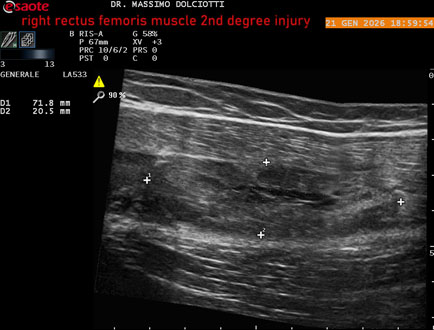

Data inserimento: 23/01/2026

Ecografia del: 21/01/2025

Strumento: Esaote MyLab Eight

Sonda: Lineare Multifrequenza 3-13 MHz

Età Paziente: M 23 anni

Motivazione dell'esame: dolore al terzo prossimale della coscia destra da tre giornii.

Commento all'esame: le immagini ed il video documentano, al terzo prossimale del muscolo retto femorale destro, area disomogenea, ipoecogena, delle dimensioni di 35 mm per uno spessore di 18 mm, misura ottenuta per asse corto o trasversale, e di 71 mm x 20 mm, misura ottenuta per asse lungo o longitudinale, da ricondurre a lesione muscolare di 2° grado con modica raccolta sieroematica intramuscolare.

Conclusioni: lesione di 2° grado del muscolo retto femorale destro (2nd degree injury of the right rectus femoris muscle).